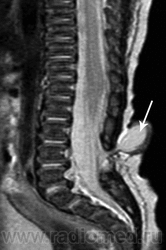

Терминальное миелоцистоцеле

Приложения:

3.cover_.giff20.medium._terminal_myelocystocele..giff21.medium._terminal_myelocystocele..giff22.medium._terminal_myelocystocele..gif